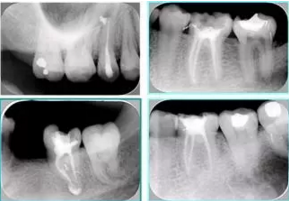

2. X 線片

共有 4 張 X 線片,分別是術(shù)前、診斷絲 、主牙膠尖確認(rèn)、術(shù)后。

( 1 )術(shù)前:術(shù)前 X 線片用來了解牙齒的大概情況。術(shù)前預(yù)期為多根牙時 X 線片應(yīng)偏頭拍攝。

( 2 )診斷絲:根據(jù)術(shù)前 X 線片進(jìn)行開髓、根管的初步預(yù)備后,需要插入診斷絲,用來指示工作器械位置。常用 10 號或 15 號擴(kuò)大器作為診斷絲插入牙髓腔。

( 3 )主牙膠尖確認(rèn):通過術(shù)前預(yù)期和診斷絲診斷,明確工作長度、牙根走向,進(jìn)行根管預(yù)備。之后應(yīng)進(jìn)行主牙膠尖(中銼)確認(rèn),已明確根管是否適合充填。

( 4 )術(shù)后:觀察治療效果。

6. 術(shù)后 X 線片

術(shù)后 X 線片用來評定根管充填 長度、致密度(管壁清晰、側(cè)枝)等指標(biāo)。

圖為根管充填術(shù)后 X 線片。圖中可見,根管充填較好。右下圖有白色小點,為側(cè)方加壓導(dǎo)致糊劑擠出所致,表明根管充填比較致密。

致密、恰到好處的充填可去除干凈根管里感染灶,機(jī)體逐漸恢復(fù)。

多根牙時候需進(jìn)行偏移投照,正位投照無法說明具體哪根牙根管充填效果。